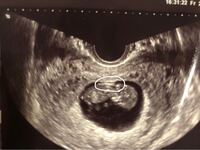

今日心拍確認できました 胎嚢の横にある黒い丸は何なのでしょう な 妊活 教えて Goo

6w1dで胎嚢しか確認できませんでした こんにちは さっそくですが 妊活 教えて Goo